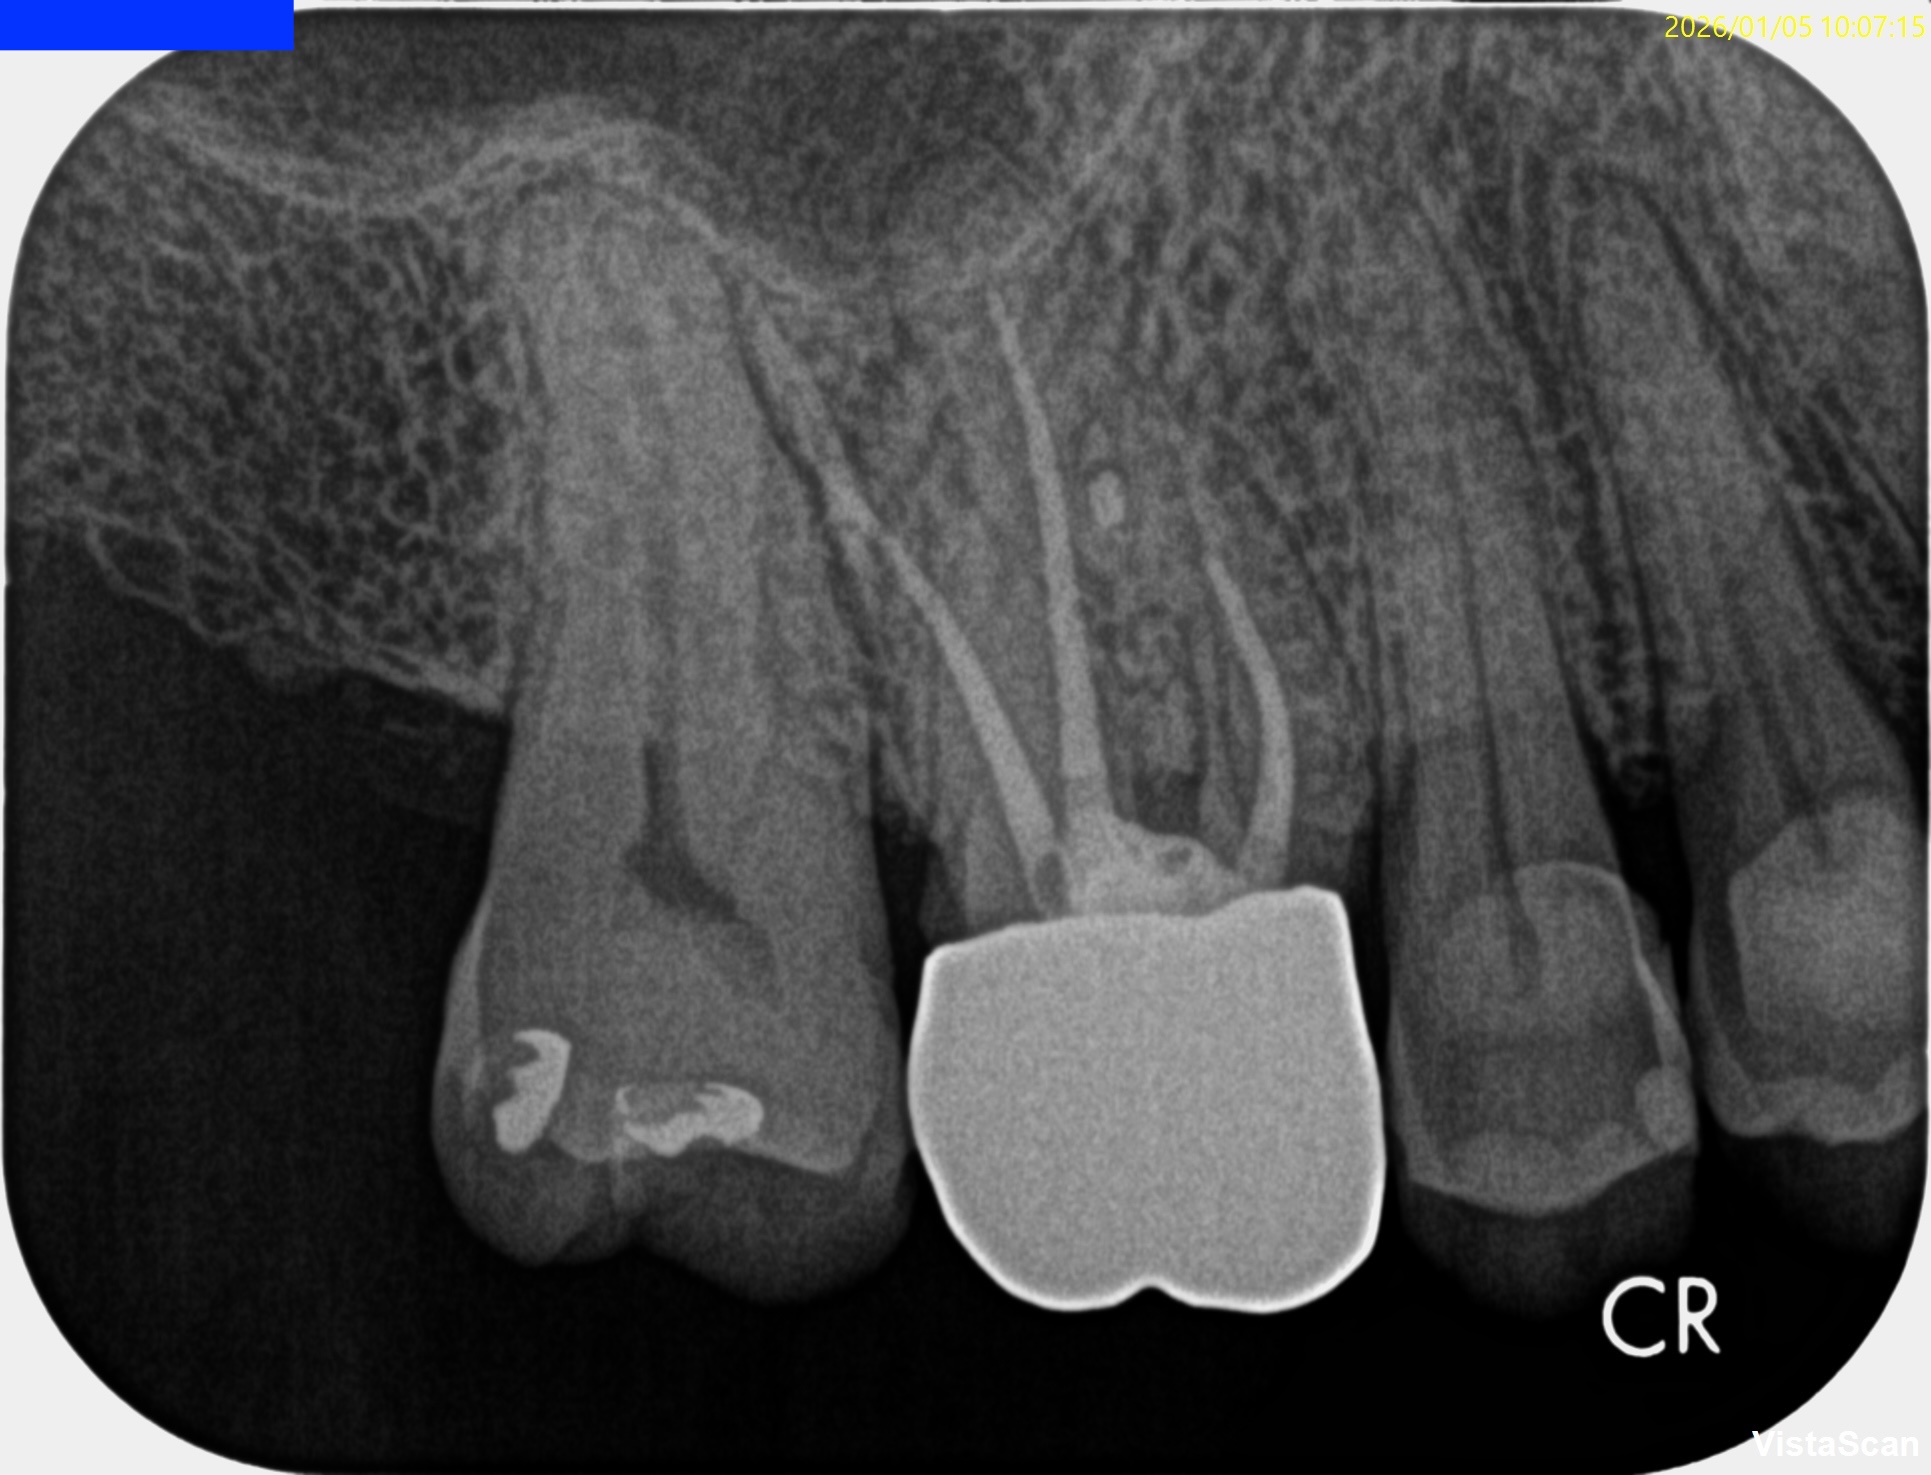

#3 RCT 1yr recall(2026.1.5)

DBの歯槽骨はまだ回復中(Healiing)だが臨床症状は消失した。

ということでまた来年も経過を見ることとなった。

またその模様をお伝えしたい。